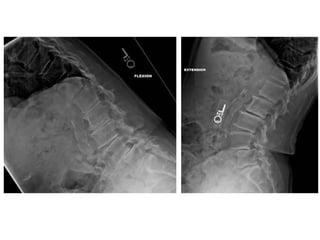

Lumbar Spine-Lateral

Position

• Make the patient to lie on the x-ray table in lateral position.

• Mid saggital plane should be parallel to the center of the

table.

• Hands are fold & kept on the head & knees are flex & small

foam pads are kept to avoid movement.

• Small foam pad are kept under the lumbar spine to reduce the

lumbar arch & lumbar lordorsis.

• Radiation Production given to the patient.

Tube Centering

• Center to the level of lower costal margin at the level of L2 &

L3 level.

Cassette centering

• The lower border of the cassette 2 inch below the ASIS.

Exposure Settings

Distance Focal Spot Grid kV mAs

Tube

Angulation

Cassette

Size

100 cm Large Yes 70-75 120-160 0° 12"x15"